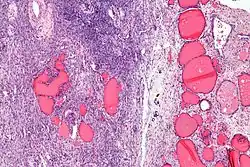

| Micrograph of a struma ovarii. Characteristic thyroid follicles are seen on the right, and ovarian stroma on the left. H&E stain. | |

Low magnification

Low magnification -